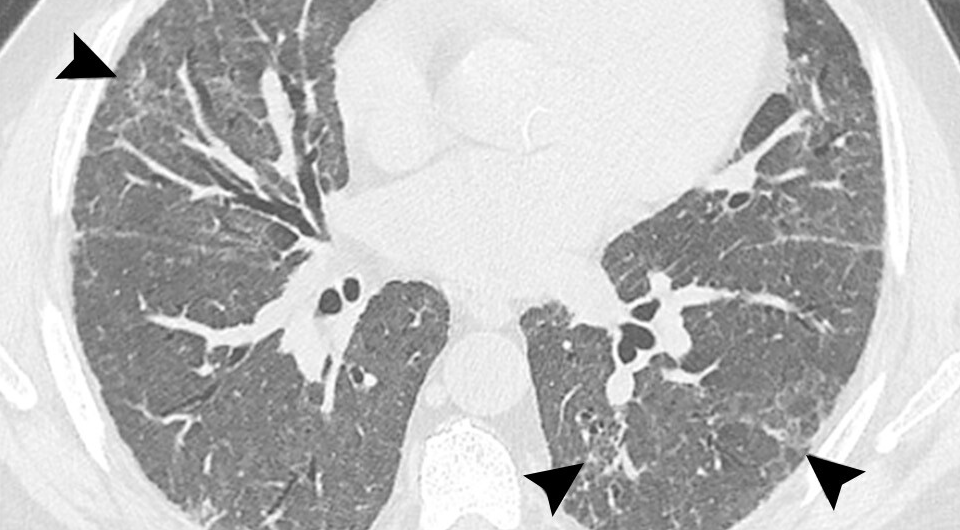

Международная группа врачей во главе с Анной Ритой Ларичи (Anna Rita Larici) из Католического университета Святого Сердца опубликовала в журнале Radiology консенсус по проведению томографических исследований среди больных после перенесенного ковида. Врачи рекомендуют проводить контрольную томографию органов грудной клетки только тем пациентам, у которых дыхательные нарушения, продолжающиеся более двух месяцев, не проходят или ухудшаются, хотя минуло более трех месяцев после перенесенной инфекции. Таким образом можно избежать избыточного облучения пациентов.

Yoon et. al / Radiology, 2025

В среднем у половины пациентов, которых госпитализируют с ковидом, можно найти изменения на томограмме грудной клетки. В большинстве случаев они самопроизвольно разрешаются, поэтому медики призывают избегать лишних диагностических процедур. Кроме этого, в консенсусе врачи также советуют использовать правильную терминологию и не называть постковидные остаточные легочные изменения интерстициальным заболеванием легких, так как это ведет к множественным избыточным томографическим исследованиям.